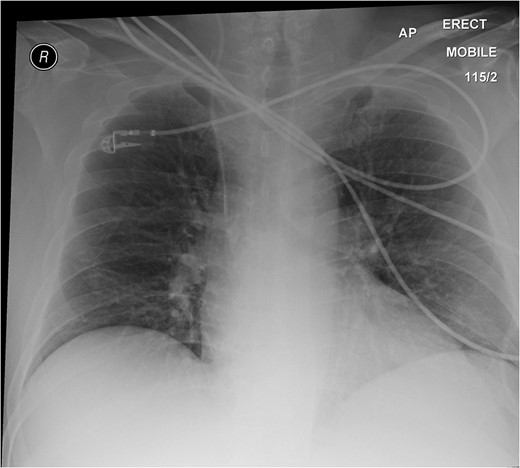

CT abdomen and pelvis (a) transverse; (b) frontal (coronal); and (c) sagittal view. An arrow indicates a blind ending sac at mid-ileal loop.

The learning point of this clinical vignette is that Meckel's diverticulitis is often clinically indistinguishable from appendicitis especially in adult patients. Computed tomography (CT) has become an invaluable tool for the evaluation of abdominal pain. CT scanning is useful in demonstrating acutely inflamed diverticula, typically identified as a blind pouch off the distal small intestine and associated with bowel wall thickening and in detecting the presence of enterocolic and enterovesical fistulas.